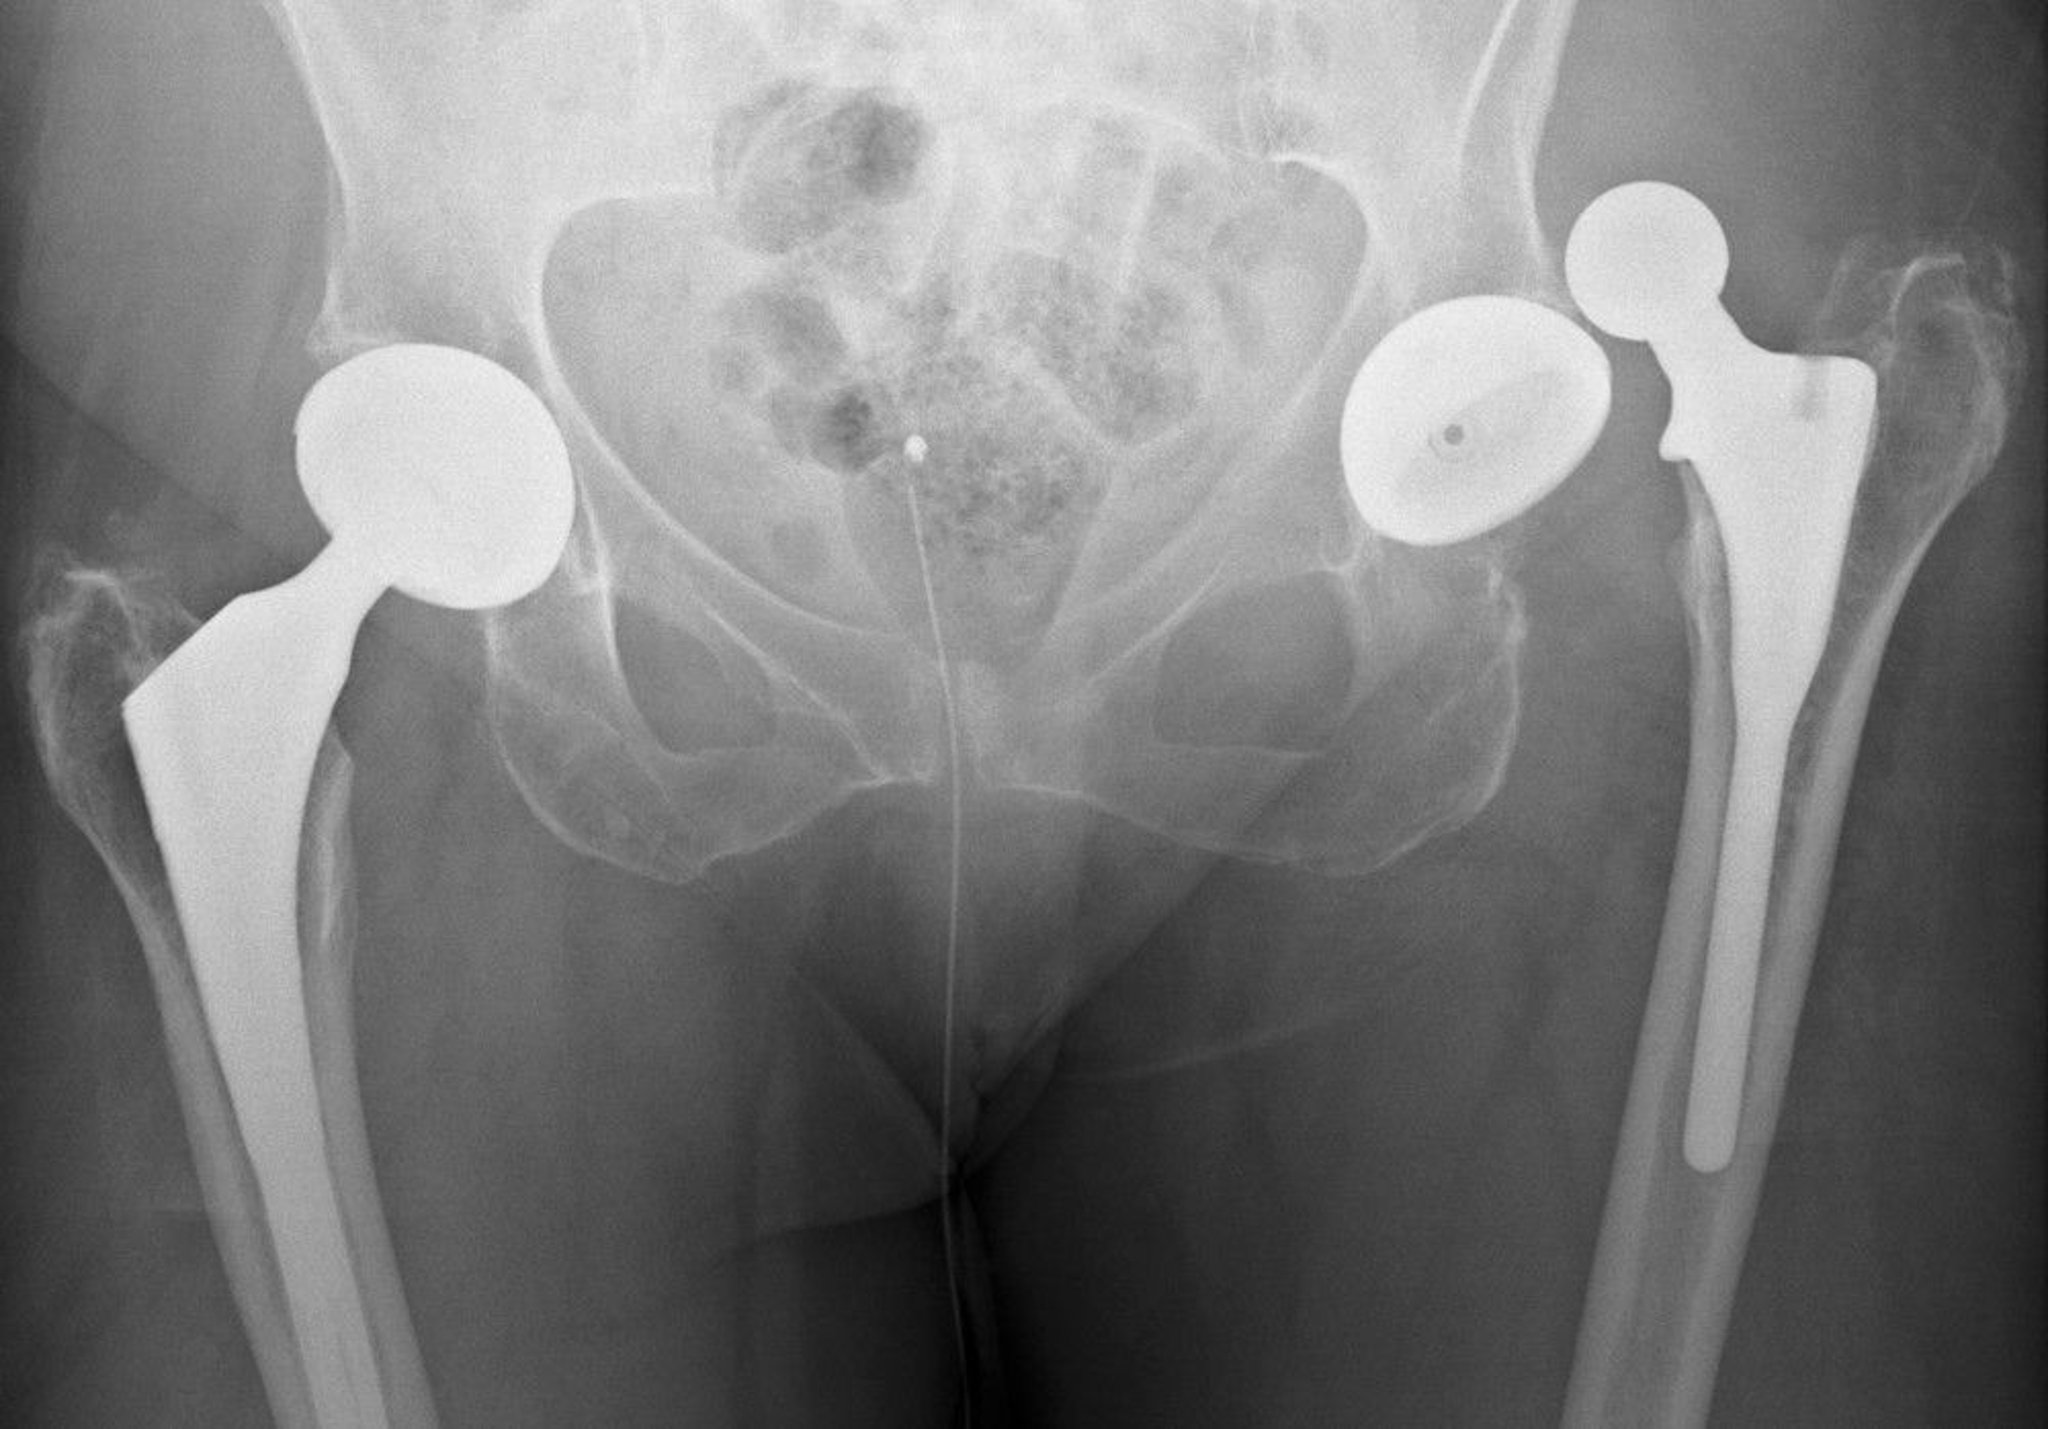

Dislocated Prosthetic Hip

This dislocation is posterior.